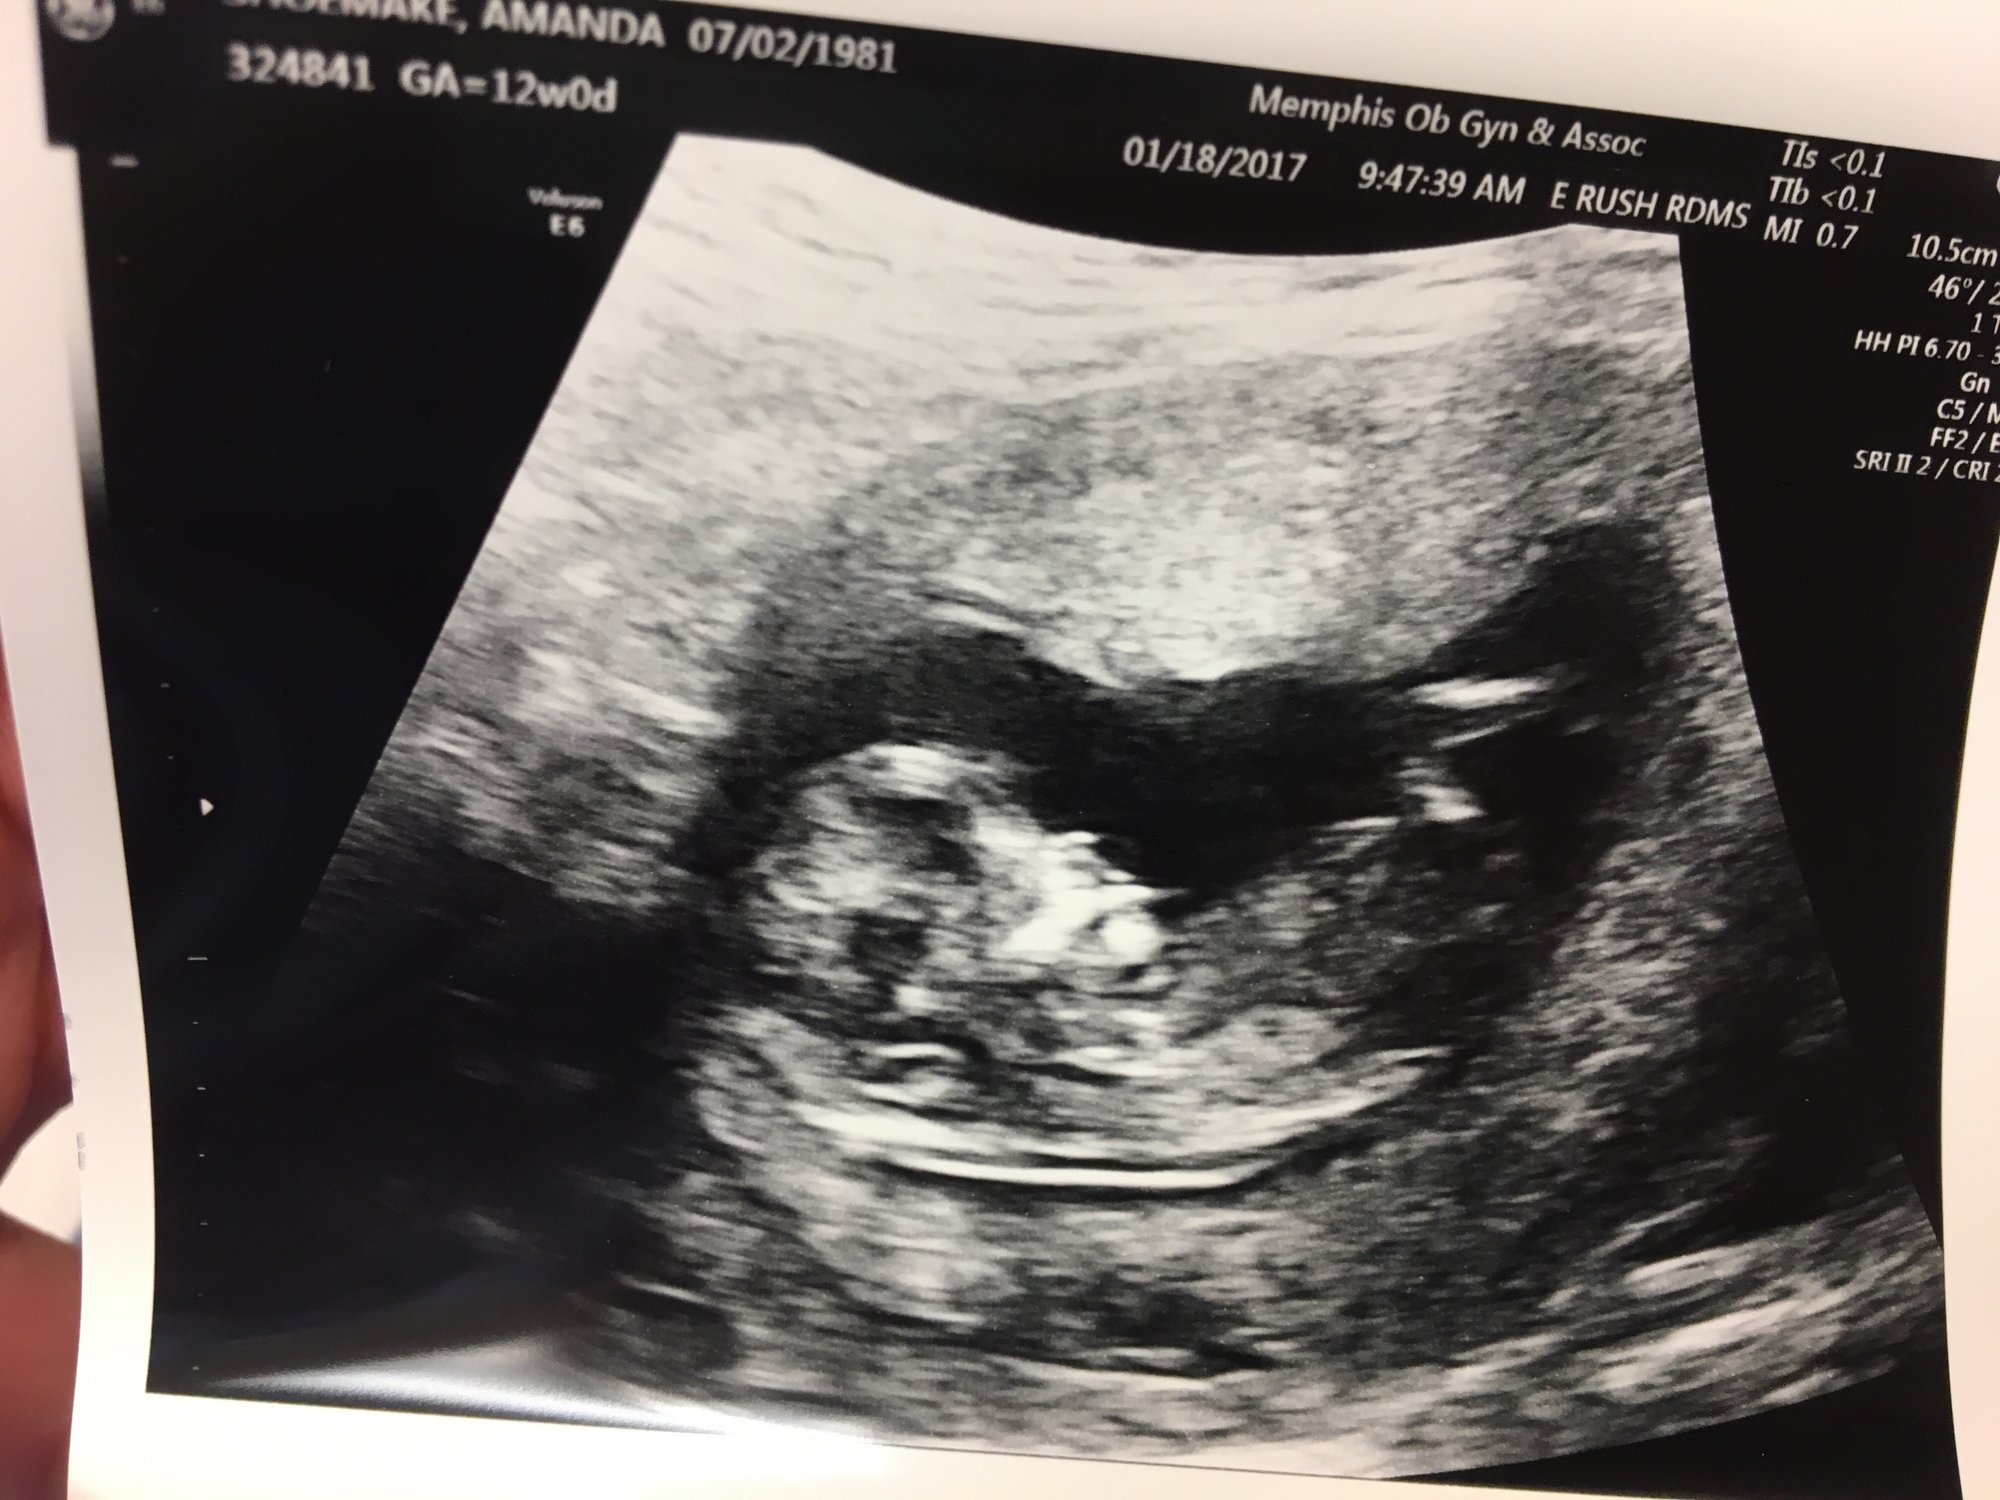

i woke up with dark, red bleeding this morning. Haven't had any bleeding this pregnancy yet. I have ultrasound at work (I'm a vet) and just peeked at baby last night. It's heart was going good and it was moving like crazy. But with two losses in the last year, I'm terrified. I stopped my progesterone two days ago, so the nurse had me do one this morning and then I'll call back when they open to be seen. I'm just so scared. And I'll have to get a Rhogam shot, because I'm O negative.

We got genetic screening back yesterday and baby I still healthy. God, please let it be okay still.

My OB got me in immediately. I'm in his waiting room now.